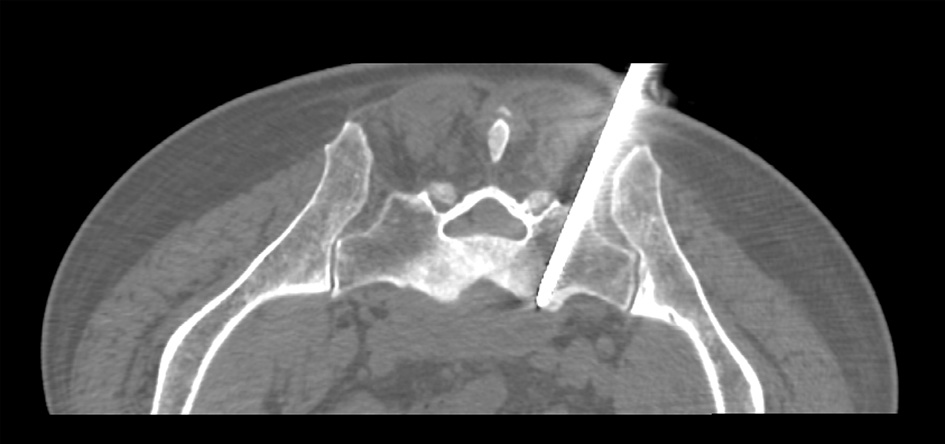

The patient was placed in a prone position and CT scan (General Electric CT VS T 64) was used to target prior to drainage. The path of the drainage catheter placement was determined in such a way that the sacral foramina, sacral canal and large vessels were avoided. After administering sufficient local anesthesia, skin incision was made, through which an 8G bone marrow biopsy needle (Medax hemax) was inserted toward the sacrum while maintaining previously set trajectory. The needle was gradually advanced through the left sacrum pedicle by applying forward pressure and rotation (Fig. 2).